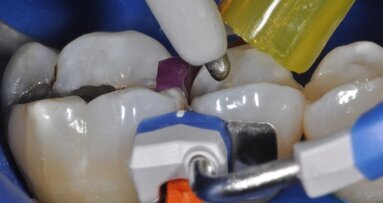

La perforazione accidentale della camera pulpare o del canale radicolare modifica in modo significativo la prognosi del dente. La riparazione della perforazione con un materiale sigillante biocompatibile come MTA può salvare i denti compromessi (Mente et al. 2014) (Figg. 3a-3e).